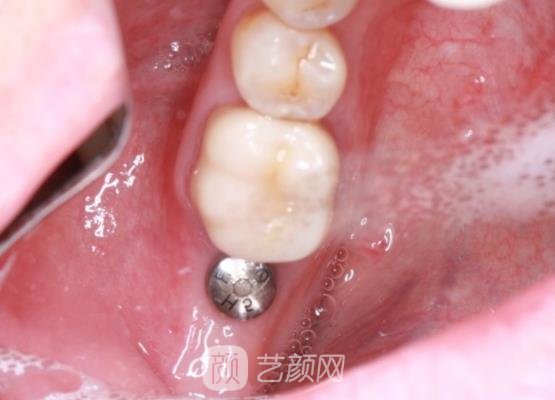

几个月以后,我的种植牙已经基本上恢复好了,可以看到我的种植牙成果,真的很自然,基本上找不到人工手术的痕迹,就像是我自己的牙齿一样,而且我的口腔也没有什么异物的感觉,手术成果真的是比较好的。